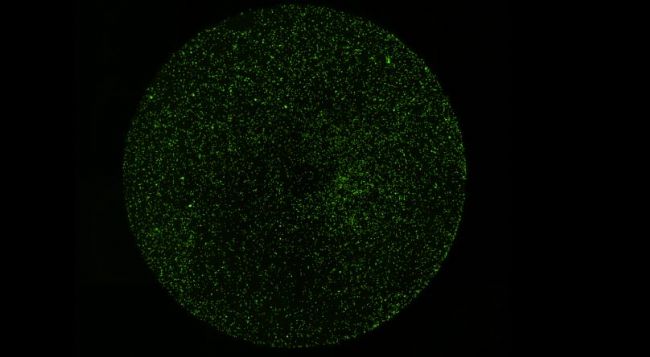

1) 0h靶細胞全孔圖像 綠色熒光圖像 明場+熒光疊加